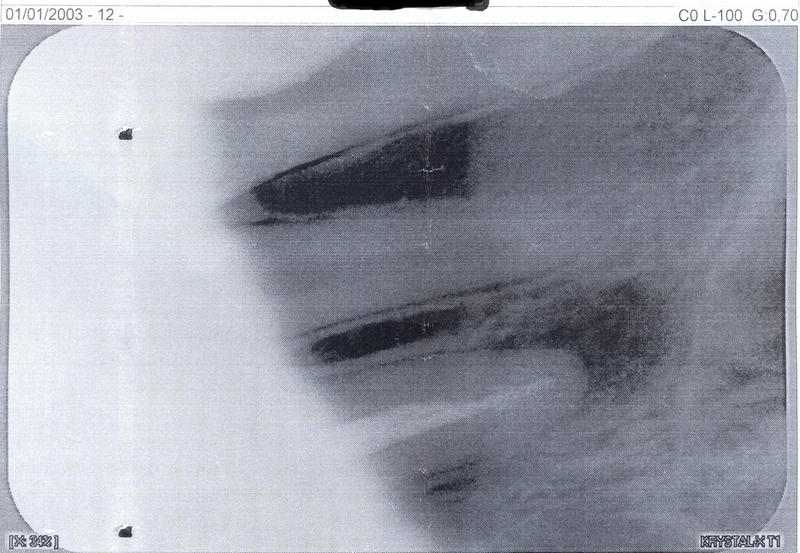

Добрый день. Хотелось узнать про передний зуб. Удаляли нерв года 3 назад, но практически все время реагирует на горячее и холодное и тд. А в апреле сильно опухла десна. Сейчас была у стоматолога сделали снимок сказали, что киста. Подскажите хирургическим ли методом ее надо удалять. Заранее спасибо.

Добрый день, уважаемая Наталья! Судя по снимку, мы имеем очень большую резекцию костной ткани вокруг этого зуба. Эндодонтическим методом такого рода кисту уже вряд ли можно вылечить. Да и резекция судя по снимку не спасет зуб. Я имею ввиду то, что кости и так мало и после резекции, а она подразумевает отсечение инфицированного корня, в кости останется 2-3 мм корня, что недопустимо и достаточной фиксации зуба в кости не будет. Возможно на снимке наложение и мы ошибаемся, поэтому настоятельно рекомендую приехать ко мне на осмотр для принятия решения. Всего вам доброго!